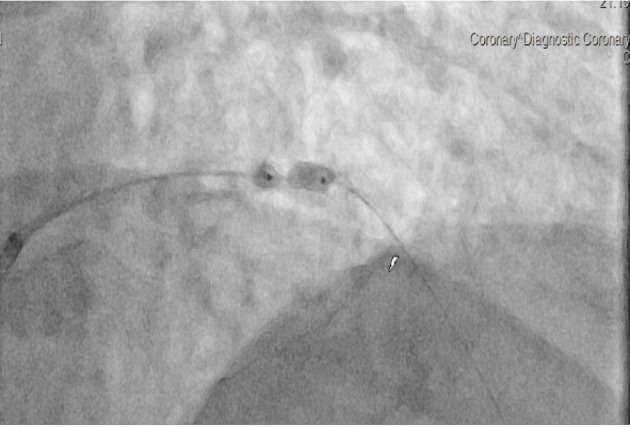

经皮冠状动脉介入治疗(PCI)中严重钙化病变的处理通常与并发症和长期不良结果的高发相关,因为钙化病变导致的冠状动脉支架扩张不理想是不良结果的最强预测因素之一。冲击波血管内碎石术(S-IVL)是一种用于严重钙化冠状动脉狭窄的最佳减积和准备的新技术,但其在急性或延迟优化未扩张支架的疗效方面的数据很少。我们报告了一例66岁男性患者,慢性全闭塞(CTO) PCI术后由于缺乏充分的预扩张和后扩张,导致LAD严重潜在钙化,支架明显扩张不足,其中S-IVL应用,支架扩张良好。S-IVL可考虑用于治疗严重的底层钙化引起的急性和晚期支架扩张不足。

Management of heavily calcified lesions during percutaneous coronary intervention (PCI) is often associated with a high incidence of complications and long-term adverse outcomes as the suboptimal coronary stent expansion due to calcified lesion is one of the strongest predictors of adverse outcomes. Shockwave intravascular lithotripsy (S-IVL) is a new technique used in the optimal debulking and preparation of severely calcified coronary artery stenoses, but there is few data on its efficacy in acute or postponed optimization of underexpanded stents. We report a case of a 66-year-old male patient with severe underlying calcification of LAD and a marked stent underexpansion after PCI of chronic total occlusion (CTO) due to a lack of adequate predilatation and postdilatation, where S-IVL was applied, resulting in excellent stent expansion. S-IVL could be considered for treating acute and late stent underexpansion caused by severe underlying calcification.